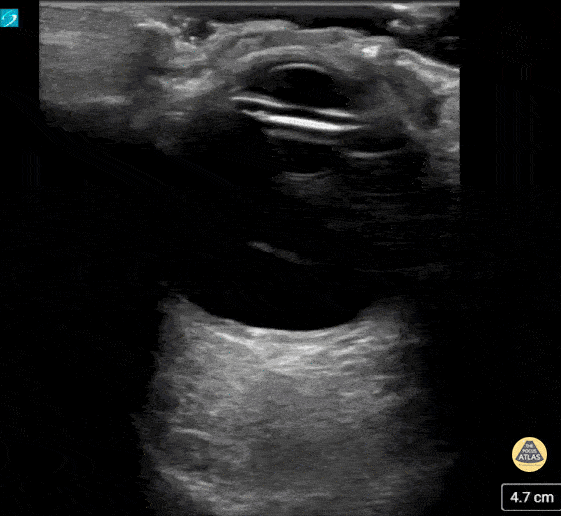

Orbital - Prosthetic Ocular Lens Subluxation

This patient presented with decreased vision on a background of advanced macular degeneration. VA in the eye had decreased from 20/150 to 20/400 on presentation. Interestingly the patient stated "I think my ocular lens has displaced." Contributed by: Colin Bell, FRCPC, DPSPC